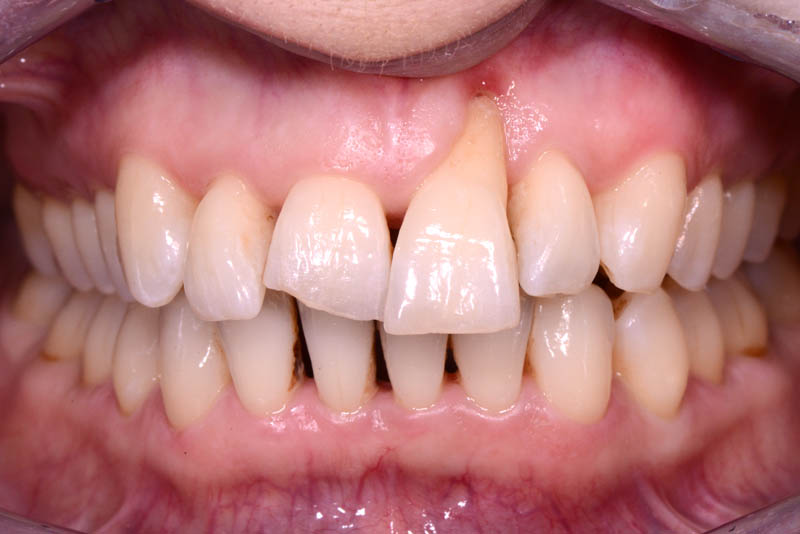

The rehabilitation of this periodontally compromised tooth required a multidisciplinary approach, combining both periodontal and orthodontic treatments.

Following an initial phase of non-surgical periodontal therapy aimed at removing subgingival calculus, Dr. Anna Mariniello performed both upper and lower alignment using a lingual, non-bracket orthodontic technique, employing active retainers applied to the lingual surfaces of the teeth.

At the end of the orthodontic treatment, a coronally advanced flap was performed according to the De Sanctis and Zucchelli technique, involving papilla preservation and connective tissue grafting, to restore the gingival contour and the papilla between teeth 21 and 22.